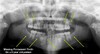

Pediatric Dental X-Rays

My child is getting shark teeth what can i do?